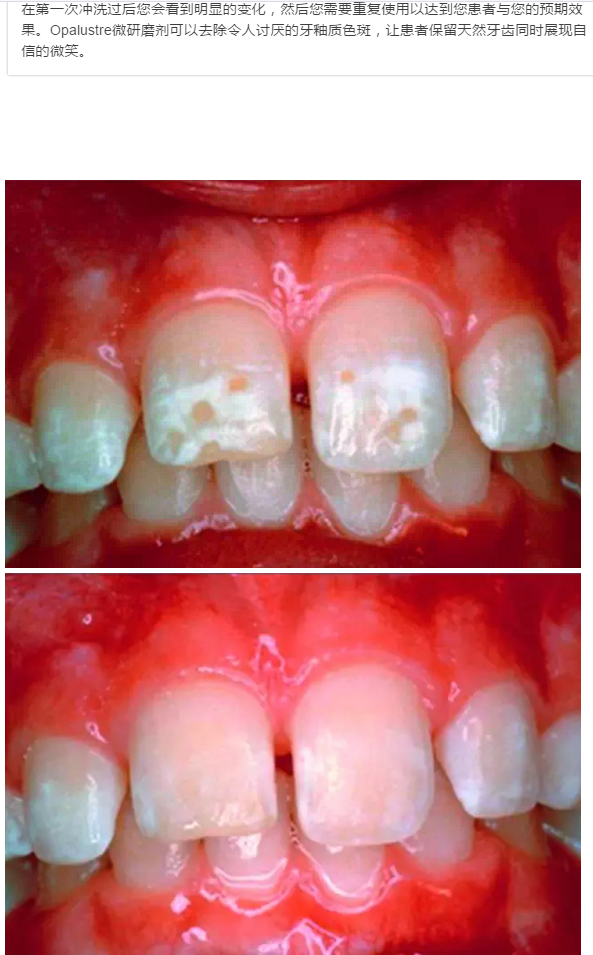

氟斑牙的新生